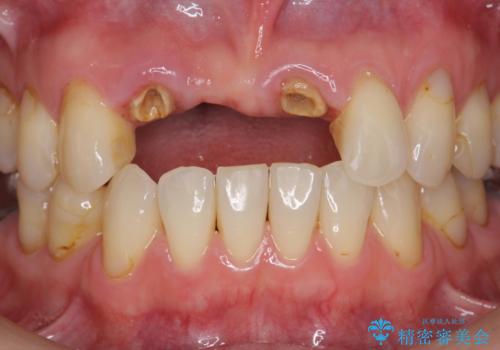

前歯が折れた 前歯部審美セラミックブリッジ治療

- ブリッジの根元が折れ、審美性の改善・治療を求めて来院されました。

保存の難しい歯を抜去しロングブリッジによる補綴を選択しました。

かみ合わせの観点からインプラント治療は難しく、入れ歯も希望されなかったためブリッジによる補綴を選択しました。